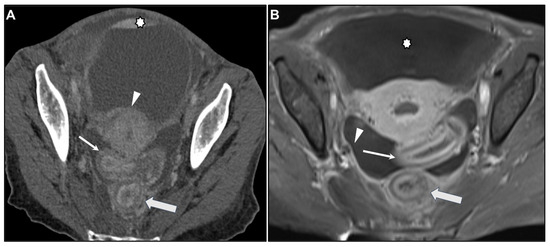

Peritoneal Carcinomatosis

Presacral Fat Tissue and Rectovaginal Septum Infiltration and T2-Weighted Imaging (T2WI) Hypointense Extramural Tumour Component

- Ha, H.K.; Jee, K.R.; Yu, E.; Yu, C.S.; Rha, S.E.; Lee, I.J.; Hee, J.Y.; Jin, C.K.; Kun, C.P.; Ho, Y. CT features of metastatic linitis plastica to the rectum in patients with peritoneal carcinomatosis. AJR Am. J. Roentgenol. 2000, 174, 463–466. [Google Scholar] [CrossRef]